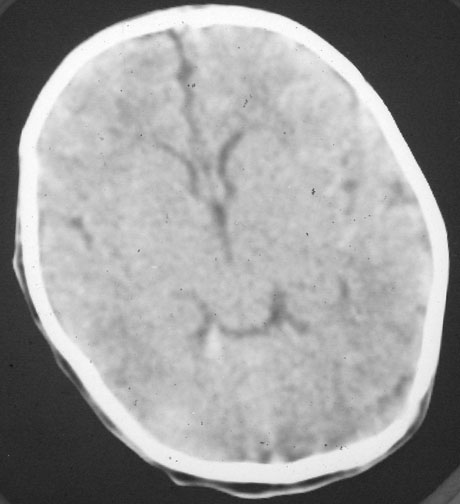

以下是引用rjg199343在2007-1-24 23:08:00的发言:[br]纵裂池、小脑幕、双侧脑室内高密度影,符合脑室、蛛网膜下腔出血。

以下是引用jiangjing在2007-1-24 23:31:00的发言:[br]纵裂池、小脑幕、双侧脑室内高密度影,符合脑室、蛛网膜下腔出血